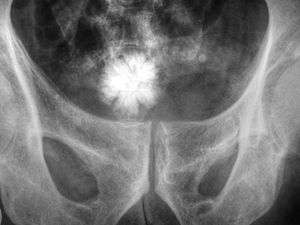

Jackstone calculi are rare bladder stones that have an appearance resembling toy jacks. They are almost always composed of calcium oxalate dihydrate and consist of a dense central core and radiating spicules. They are typically light brown with dark patches and are usually formed in the urinary bladder and rarely in the upper urinary tract. Their appearance on plain radiographs and computed tomography in human patients is usually easily recognizable. Jackstones often must be removed via cystolithotomy.[10]